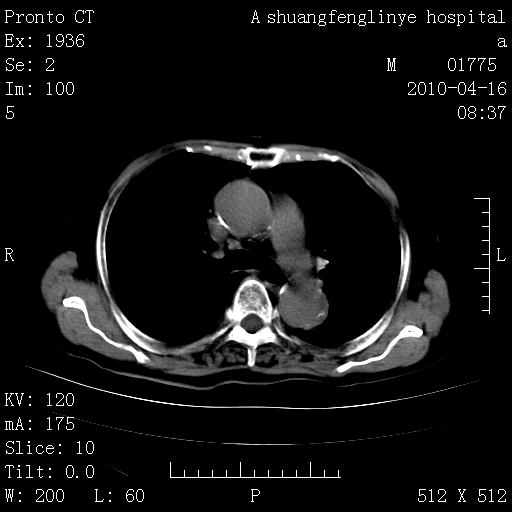

标题: CT25784:咳痰、请会诊!结核?

老年肺间质纤维化,肺动脉高压-----肺心病。

慢支肺气肿,左上陈旧性结核,主动脉冠脉钙化

典型 夹层动脉瘤。 内膜瓣钙化移位

1)左肺上叶结核(纤维、增殖病灶)。2)冠状动脉及主动脉钙化。

1)左肺上叶结核(纤维、增殖病灶)。2)冠状动脉及主动脉钙化。肺动脉高压